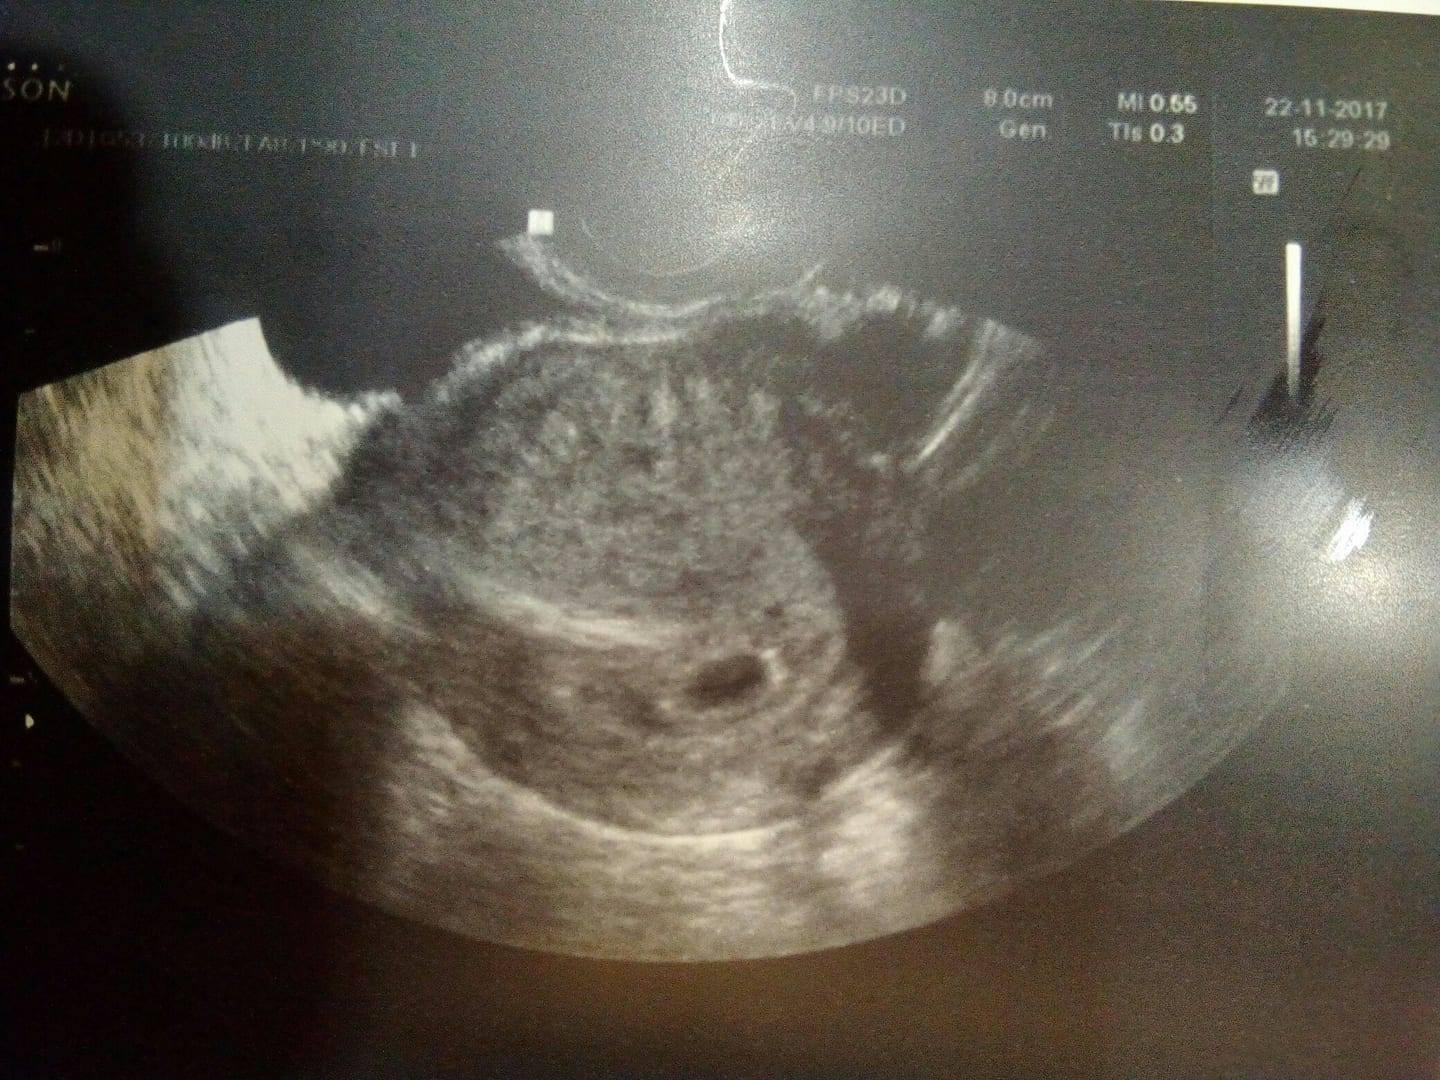

@krisatko :D ja jdu zitra poprve k dr (4+6) asi je jste brzy na to, aby neco videl, ale po tim bráni léku na prolaktin chci byt radši pod kontrolou. Tolik si preju, aby bylo vse v pořádku an za dva tDny jsem viděla ❤️ Pak se mi strasne uleví

@kockakacka Já jdu zítra na druhou. Kolikátý tt těžko říct u mně. Mám nepravidelný cyklus takže už to že se zadařilo je zázrak. Ale podle mě už by teď něco mělo být vidět, minule byl žloutkový váček. 🙂

@kockakacka ale tak gestační váček alespoň si myslím, že už tam bude ;)

@kockakacka ale proč ne :D hele, když už tam jdeš. Já byla prvně 5+4tt a když si vezmu, že ten menší váček je o týden mladší, což je 4+4tt a je tam jen piditečička.

Ale najeď si na google a do vyhledávače dej 4+6tt UZ tak ti vyjede, jak přibližně může vypadat 🙂